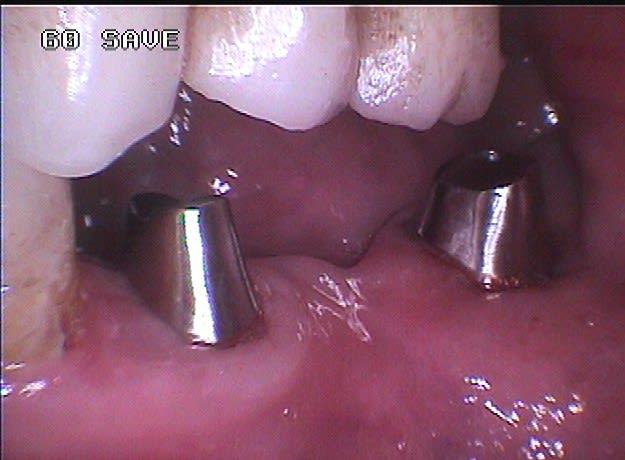

Cette même patiente, pimpante pour ses 90 ans et pleine de gaieté, viens me voir pour son nouvel appareil du bas qu'elle ne supporte pas. Avec surprise, je découvre dessous des chicots abandonnés par son ancien dentiste avec des inflammations gingivales. Radios prises, je lui propose de tenter de les récupérer pour lui réaliser des bridges en remplacement de son appareil, à l'inverse de ce qui se fait habituellement.

La racine résiduelle de la 37 était logée au fond d'un entonnoir gingival au ras de l'os et la 46 était trop délabrée pour la conserver entière. Après quelques séances de gingivoplasties et de tailles, le pari était gagné et les bridges ont pu être scellés, la patiente était radieuse!